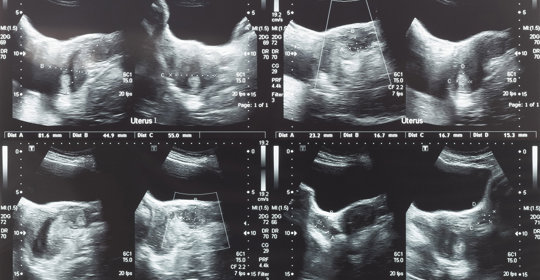

胎兒水腫:瞭解成因、預防與治療方法,守護母嬰健康